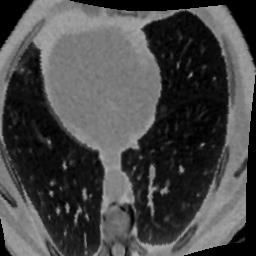

In clinical practice, well-aligned multi-modal images, such as Magnetic Resonance (MR) and Computed Tomography (CT), together can provide complementary information for image-guided therapies. Multi-modal image registration is essential for the accurate alignment of these multi-modal images. However, it remains a very challenging task due to complicated and unknown spatial correspondence between different modalities. In this paper, we propose a novel translation-based unsupervised deformable image registration approach to convert the multi-modal registration problem to a mono-modal one. Specifically, our approach incorporates a discriminator-free translation network to facilitate the training of the registration network and a patchwise contrastive loss to encourage the translation network to preserve object shapes. Furthermore, we propose to replace an adversarial loss, that is widely used in previous multi-modal image registration methods, with a pixel loss in order to integrate the output of translation into the target modality. This leads to an unsupervised method requiring no ground-truth deformation or pairs of aligned images for training. We evaluate four variants of our approach on the public Learn2Reg 2021 datasets \cite{hering2021learn2reg}. The experimental results demonstrate that the proposed architecture achieves state-of-the-art performance. Our code is available at https://github.com/heyblackC/DFMIR.

翻译:在临床实践中,如磁共振(MR)和光谱成像(CT)等非常相近的多模式图像可以一起为图像制导疗法提供补充信息。多模式图像登记对于这些多模式图像的准确匹配至关重要。然而,由于不同模式之间复杂的和未知的空间通信,这仍然是一项非常艰巨的任务。在本文中,我们提议采用新的、基于翻译的、不受监督的变形图像登记方法,将多模式登记问题转换成单一模式。具体地说,我们的方法包括一个无歧视翻译网络,以便利对登记网络的培训,以及一种有偏差的对比性损失,以鼓励翻译网络保存对象形状。此外,我们提议取代在以往多模式图像登记方法中广泛使用的一种对抗性损失,目的是将翻译的输出纳入目标模式。这导致一种不统一的方法,不需要地面图解或对齐图像来进行培训。我们评估了公共学习2MReg20的四种变式方法,我们在公共实验2Regmal-ress productions 2021我们提议的实验性结构中实现了2021号的运行结果。